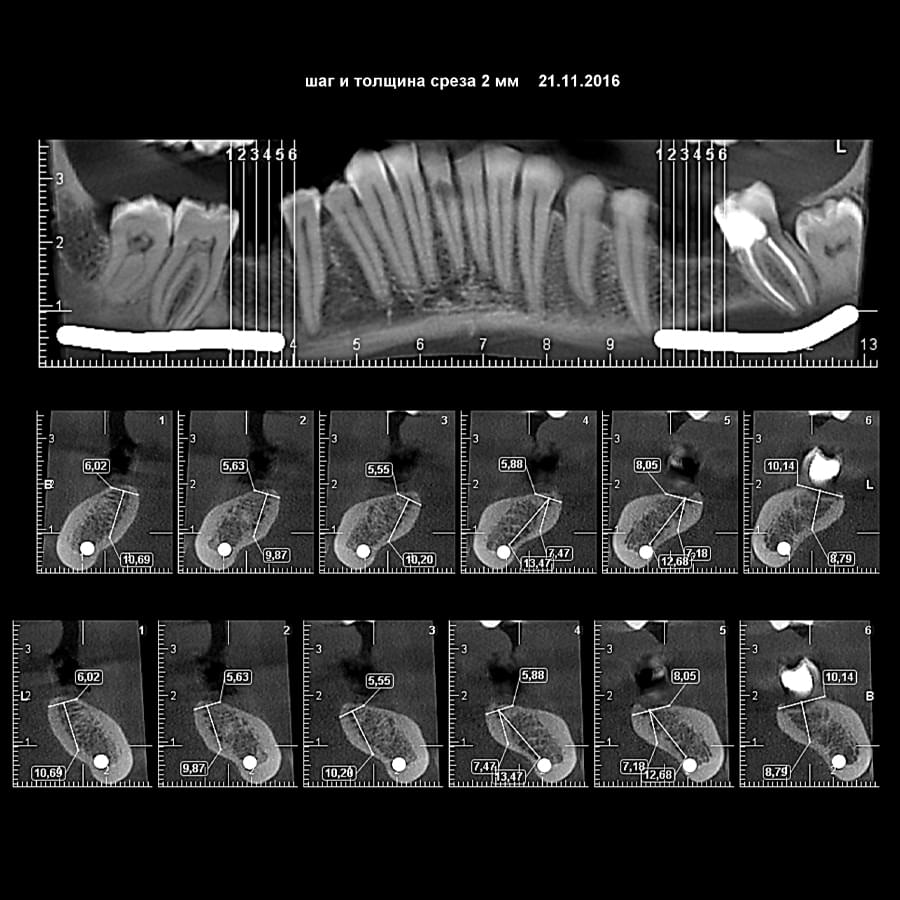

Мережа діагностичних центрів "МАЙРЕЙ ЛАБ" забезпечує точну та надійну діагностику

щелепно-лицевої ділянки з мінімальним ризиком для пацієнтів.

Ми використовуємо найсучасніше обладнання відомого виробника PLANMECA, що дозволяє отримувати високоякісні зображення за короткий час. Крім того, ми маємо власний сервер, на якому створюємо окрему скриньку для кожного лікаря, що забезпечує максимальну зручність та ефективність роботи.

Наша команда має великий досвід у діагностиці що дозволяють проводити точну діагностику

та вчасне виявлення проблем.